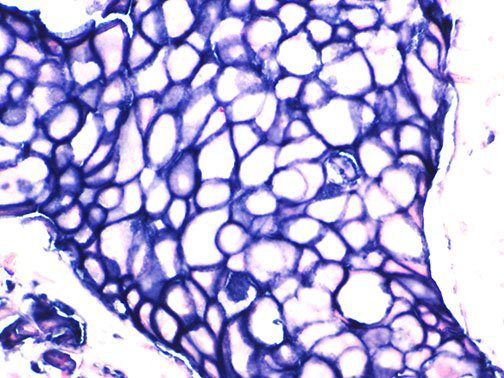

This activation induces inflammatory monocytes to highly express IL-6, starting a localized and then systemic cascade effect that results in hyperproduction of IL-6, which accelerates the inflammatory process. Because IL-6 also increases vascular permeability, excessive levels cause blood vessels to become very leaky. This, along with clotting factors released from vascular endothelial cells, stimulates the coagulation cascade, resulting in microthrombosis (tiny clots), which leads to ischemia and tissue death of the kidney, intestines, heart, liver, brain and extremities.